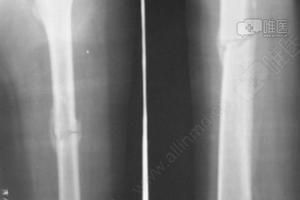

骨痂图对比,骨折骨痂形成图片对比

骨折骨痂形成图片对比

骨痂生长过程图对比

骨折后骨痂形成图片

骨痂生长过程图骨折

骨痂生长过程图图解

骨痂生长过程图

骨痂生长过程